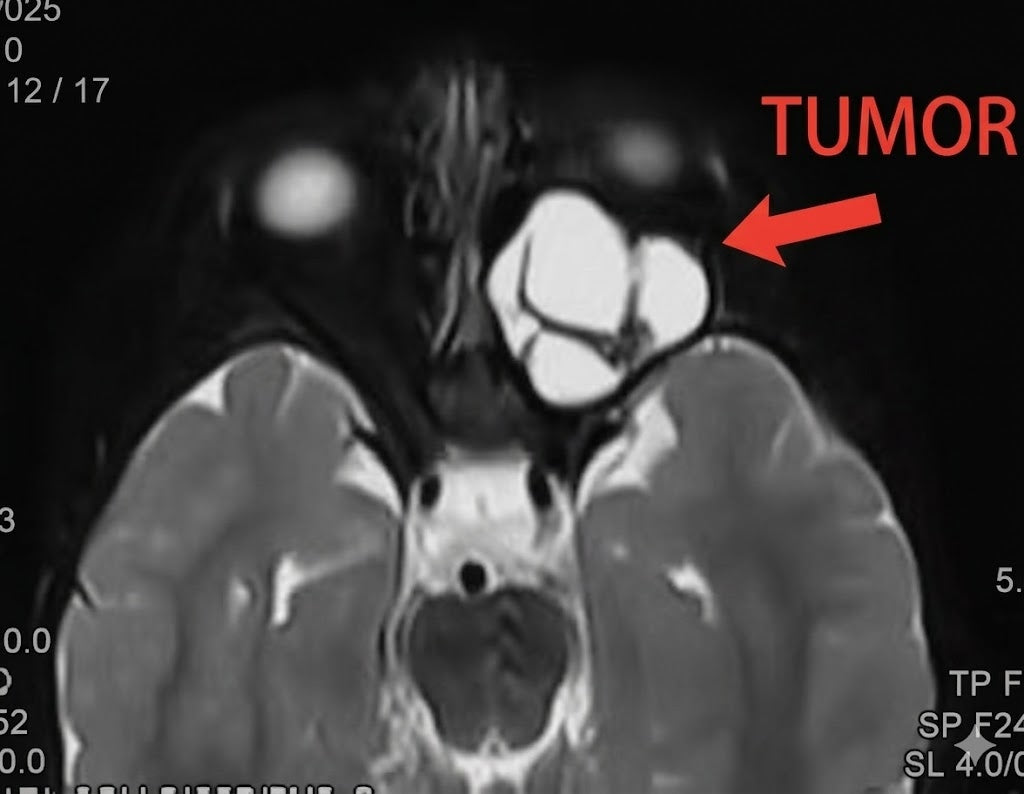

A 2-year-old child with a massive orbital teratoma extending through the infraorbital fissure into the pterygopalatine fossa.

Anatomical Risk: Adherence to the maxillary artery poses a fatal hemorrhage risk.

Functional Threat: Severe optic nerve compression with high risk of permanent blindness.